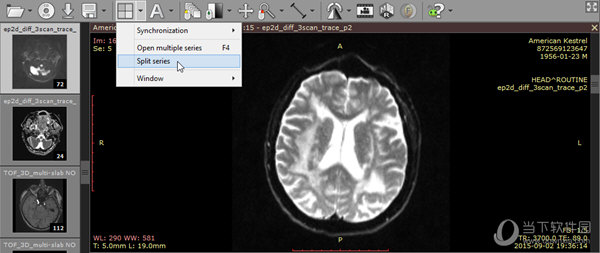

6、多系列观赏:可以在多个面板中同时打开多个系列的一个或多个研究用于比较。